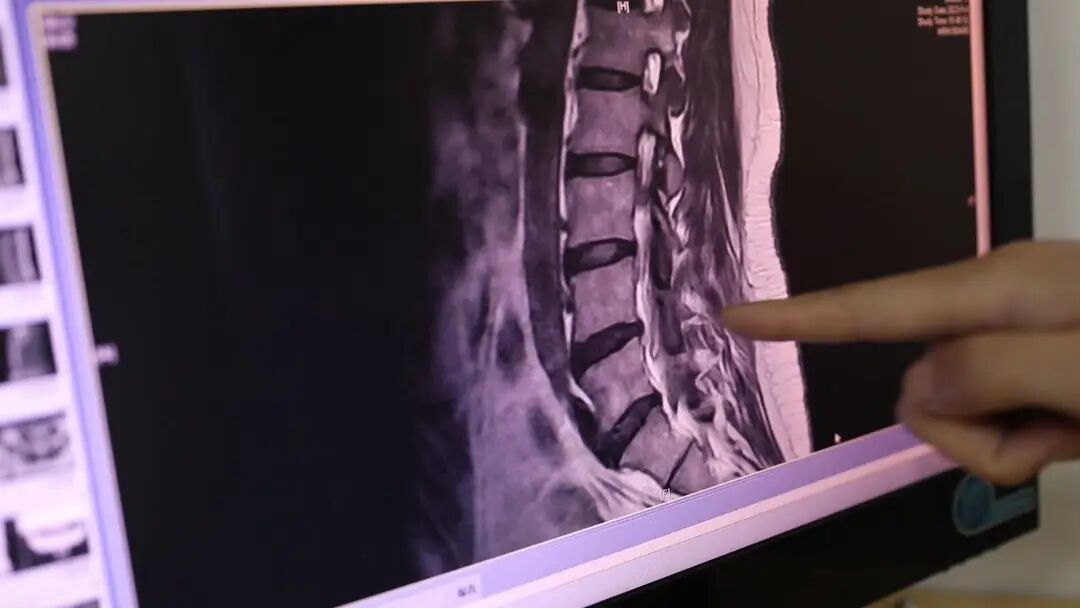

这几天,淄博市市立医院骨科病房

就接收了一名由于长期侧躺看手机

而出现腰背部疼痛的患者

淄博市市立医院骨科副主任医师 李栋:从片子上看,它主要的问题是发生在腰4/5和腰5/骶两个阶段,因为这两个阶段的椎间盘,相比于其他阶段来讲,他是超过了椎体后缘,有轻度椎间盘抛出情况。如果说长时间一个姿势躺着,因为重力作用,可能也会对,脊柱侧屈发生影响,而严重的可能会引起椎间盘一侧轻微的膨隆膨出,甚至说会引起腰椎间盘突出。